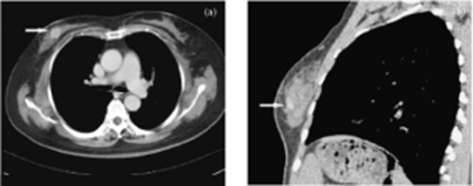

PET/CT

This is a new advanced imaging tool that combines the modalities of CT (computed tomography) and PET (positron emission tomography) in one imaging procedure. The PET scan detects the metabolic signal of actively growing cancer cells in the body whilst the CT scan provides a detailed picture of the internal anatomy that shows the location, size and shape of cancerous growth. The results of PET/CT scans are digitally fused together providing complete information on cancer location and abnormal cellular metabolism. PET/CT combines the high sensitivity of PET with the high anatomical spatial resolution of multislice CT. This integrated approach of PET and CT technologies into a single imaging procedure permits accurate tumour detection and anatomical localisation for many cancerous growths.